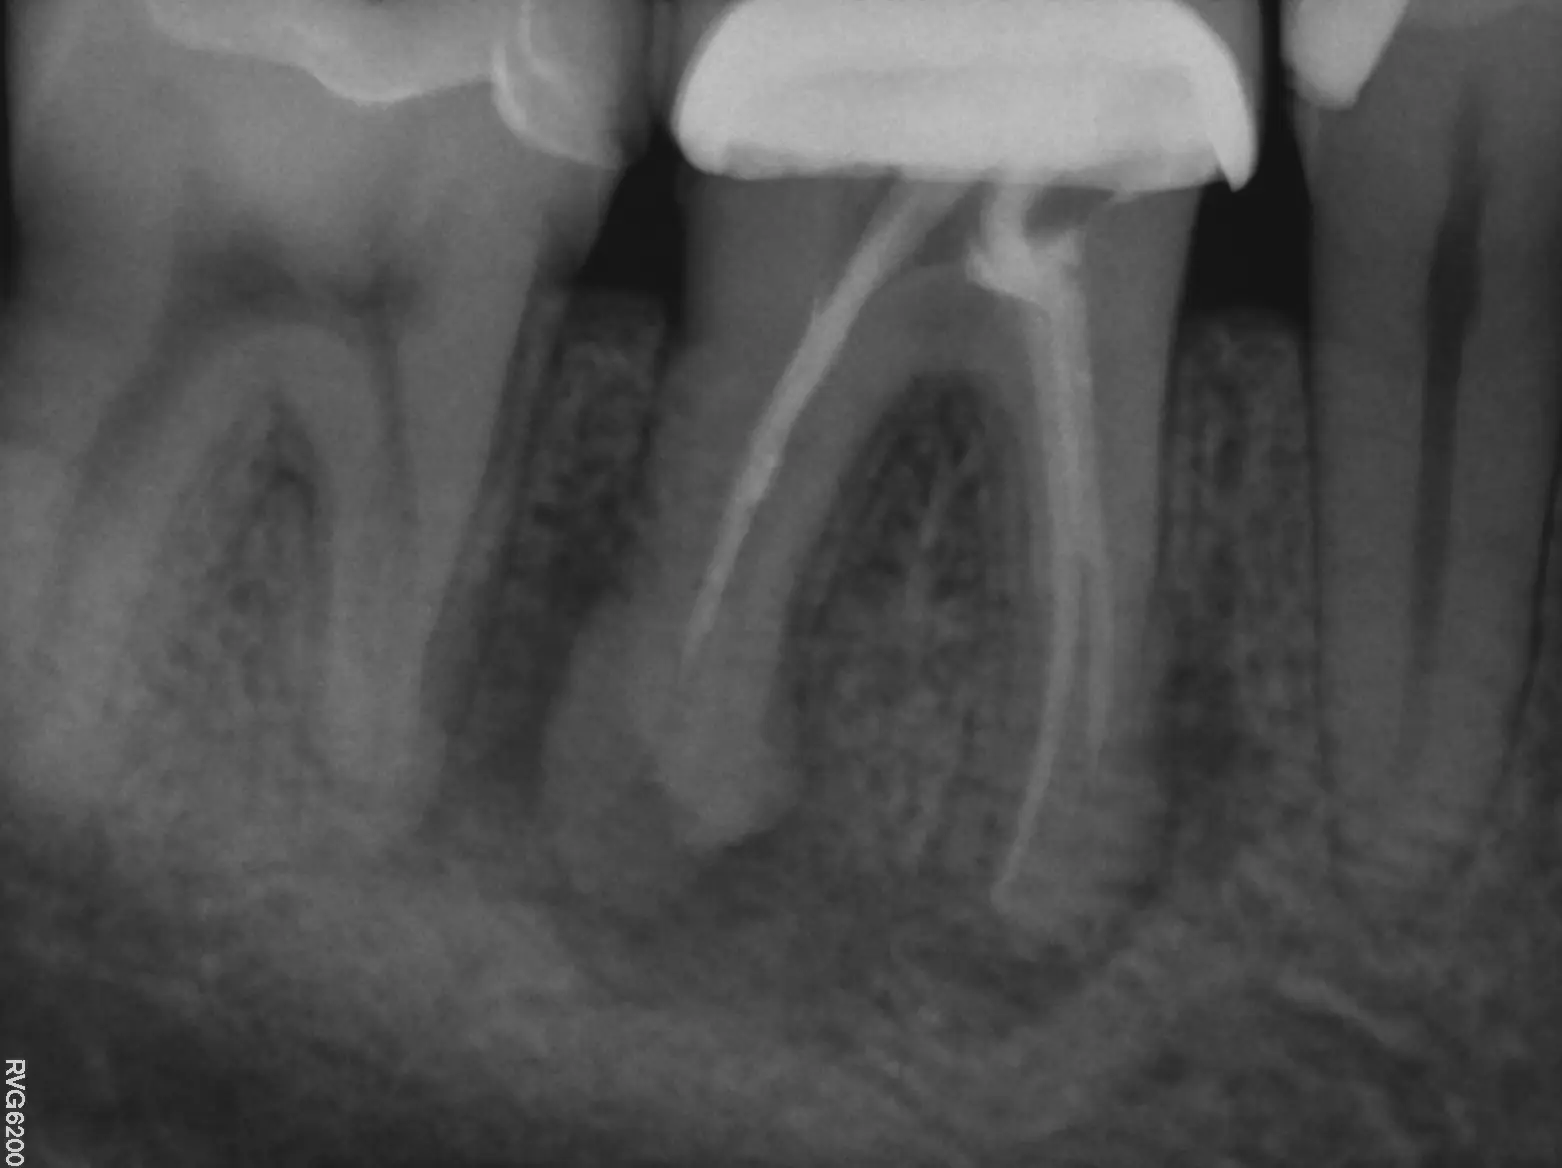

To find the source of your dental pain, your endodontist will begin by performing a comprehensive exam and review of your x-rays to get a complete picture of your oral health. If your tooth is infected, they will determine the extent of the infection to decide if root canal therapy will be an effective treatment.

Your general dentist may have already taken some recent X-rays of your teeth before your visit with us. To arrive at a diagnosis and recommend treatment, we require specific angles of the tooth that can only be obtained with in-house imaging. We will do our best to obtain the images from your referring dentist and compare them to our own, so that we can review the complete picture with you